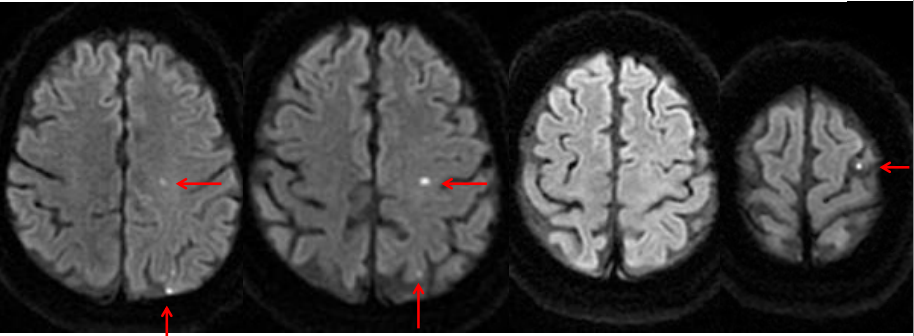

A 45 y/o woman with hypertension is resuscitated after a cardiac arrest. On day three she is able to move her face, hands, and feet, but is unable to move her limbs. A T2W1 MRI is taken at this time and is attached.

What is the general pathogenesis behind her symptoms and the MRI findings?

Hypotension secondary to cardiac arrest caused ischemia within the cerebrum, which has damaged her primary motor cortex bilaterally.

What cellular change is causing the bright vertical bands in each hemisphere?

Cytotoxic edema secondary to ischemia. The ischemia disrupts metabolism, which shuts down the Na+/K+/ATPase and causes cellular retention of Na+ and water.

Recall that on a T2W1 MRI, fluid (including water and CSF) is bright (as well as fat).

Why is the cellular change visaulized by the MRI localized to vertical bands?

This injury is a watershed infarction between the areas perfused by the ACA and MCA. The MCA area of the brain is especially susceptible to ischemia, and so its watershed area with the ACA will be the first to suffer. The bright vertical bands show cellular injury in the watershed zones across the entire cerebrum.

Why is the woman able to move her face, hands, and feet, but not her limbs?

Watershed injury across the the primary motor cortex tends to affect the proximal limbs and trunk much more severely than the hands, feet, and face.

• This is partially due to the watershed area’s location being centered over the motor homonculus’ area for the limbs and trunk,

• And partially due to the trunk and limbs being relatively small areas of the homonculus while the hands, feet, and face take up a large area of it (more sensitive/precise moving structures)

• Thus, even a small ischemic area can cause relatively severe truncal or limb weakness, whereas the majority of the larger face, hand, and foot regions tend to be spared.

Where is ACA-MCA watershed area in this picture?